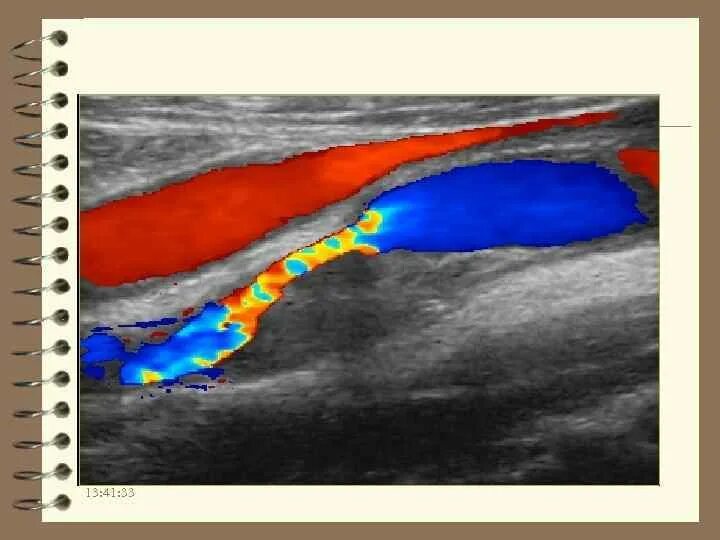

Атеросклеротическая бляшка узи